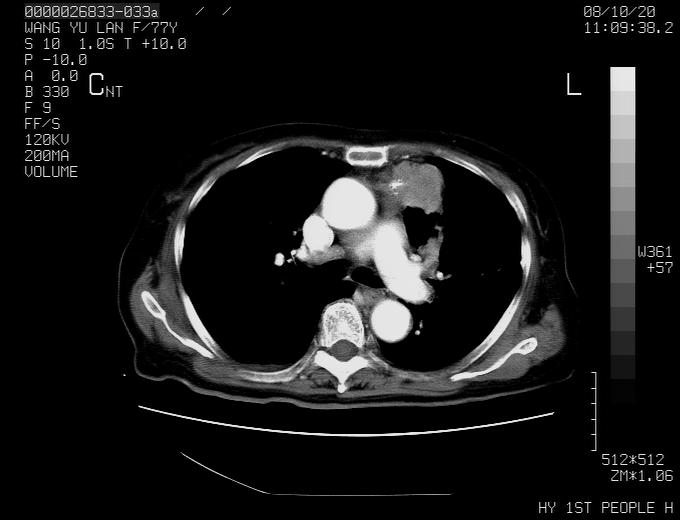

女性,77岁,胸部疼痛半月。左上肺团块影,本人考虑血管畸形,请分析

纵隔有多个淋巴结肿大,提示周围型肺癌并转移可能性大。

动脉期未见大血管同步强化,首先考虑周围型肺癌

动脉期病灶近中线侧可见星芒状与大血管同等强化密度,支持考虑血管畸形伴血栓形成,动脉期不曲型,不除外周围型肺癌

1、考虑avm可能性大。2、纵隔有肿大淋巴结,左肺上叶有炎性病变,不排除肺癌并转移可能。

左肺周围型肺癌并肺门淋巴结转移,很典型了!